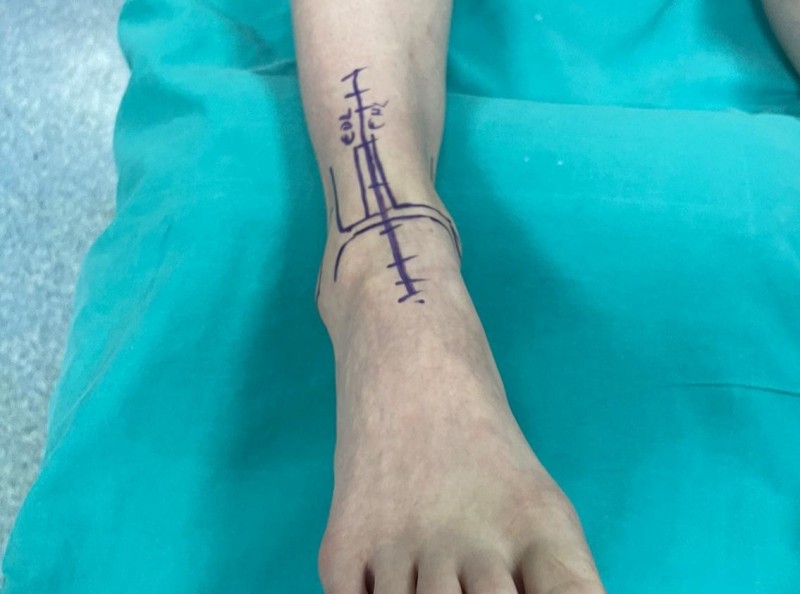

Hastanede yapılan, “Balıkesir’de ilk” nitelikli işlemlerin bir yenisi de Ortopedi ve Travmatoloji Anabilim Dalı Öğretim Üyesi Doç. Dr. Aziz Atik tarafından gerçekleştirildi. Gerçekleştirilen ameliyatla ilgili bilgiler veren Ortopedi ve Travmatoloji Anabilim Dalı Öğretim Üyesi Doç. Dr. Aziz Atik; “Lenf kanseri olan 21 yaşındaki hastamız lenf kanseri tedavisi görerek sağlığına kavuşmuş ancak ilerleyen zamanlarda aldığı tedavilerin yan etkisi olarak ayak bileği kemiğinde çürüme meydana gelmiş. Bize başvuran hastamızın eklem yüzeyi bozulmuş ve hastamız yürümekte zorlanıyor, topallıyordu. Büyük bir lezyonu olan hastamıza büyük lezyonlarda uygulanan en iyi tedavi yöntemi olan ve nadir olarak yapılan bir ameliyatla kadavra donörden kemik ve kıkırdak doku nakli gerçekleştirdik.” ifadelini kullandı. Ülkemizde kemik ve kıkırdak bankası olmadığının altını çizen Doç. Dr. Aziz Atik, yurt dışından bir donör bulmak için çalışmalar yaptıklarını ve yurtdışından kemik bulunduğunda ivedi bir şekilde ameliyatı gerçekleştirdiklerini söyledi. Ameliyatın son derece başarılı geçtiğini belirten Doç. Dr. Aziz Atik, güzel bir eklem düzeyi elde ettiklerini ve ameliyatla genç bir insanın topallamadan, ağrısız yürümesini hedeflendiklerini dile getirdi.